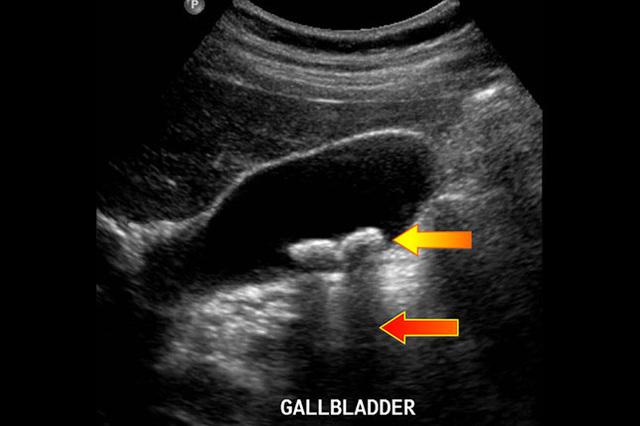

我让患者去做个上腹彩超看看,果然,彩超提示胆囊炎,并且可以看到胆囊内多发结石。